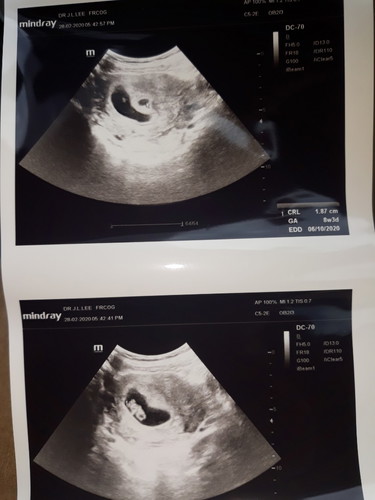

I dh 3 kali berturut2 spotting every week. So i decide jmpa doc check. Time tu 8 weeks dh. Doc check ada satu ketulan twin x jadi di luar kanung baby yg menjadi. Ketulan tu yg buat spotting. Doc beri ubt tahan kandungan n acid folic. Now dh 10 weeks, masih ada spotting lagi tiap kali perut crame. Risau gak. Hrp2 baby sihat dlm tu.